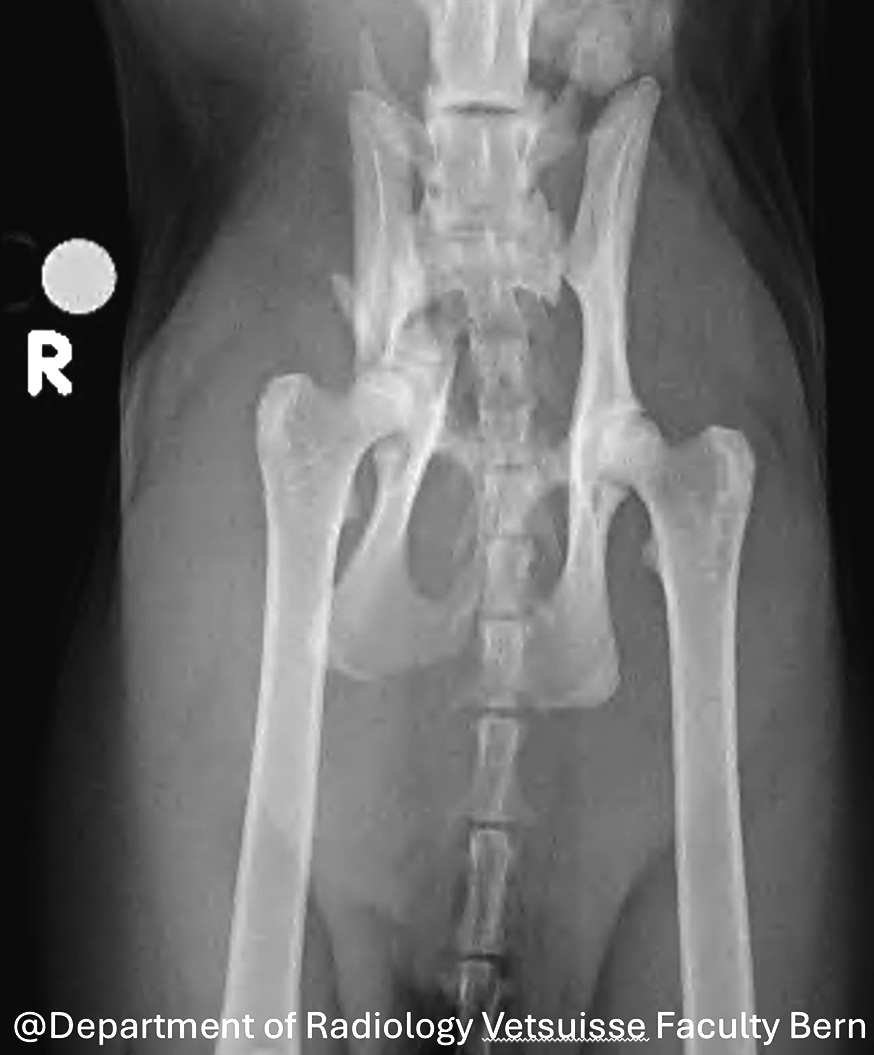

Eine Beckenstenose infolge einer fehlverheilten Beckenfraktur ist die häufigste Ursache für ein hypertrophisches oder obstruktives Megakolon bei Katzen (Abb. 1) [1], [3]. Basierend auf den Ergebnissen eines Berichts wird bei Katzen mit akuten Beckenfrakturen und medialer Verlagerung des kaudalen Ileumsegments, die zu einer Beckenverengung von mehr als 45% führt, eine frühzeitige chirurgische Intervention empfohlen [4]. Diese Studie hat jedoch keine Katzen untersucht, die konservativ behandelt wurden. Um ein irreversibles Megakolon zu verhindern, sollte jede chirurgische Intervention zur Erweiterung des Beckens innerhalb von 6 Monaten nach dem ersten Trauma durchgeführt werden.